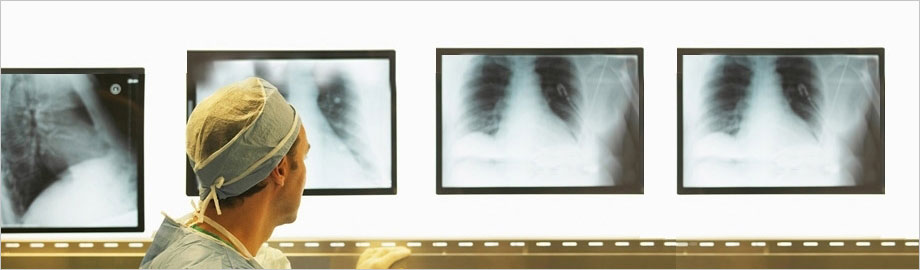

- Diagnostic and therapeutic hepatobiliary ultrasound

- Doppler study of portal system and hepatic veins